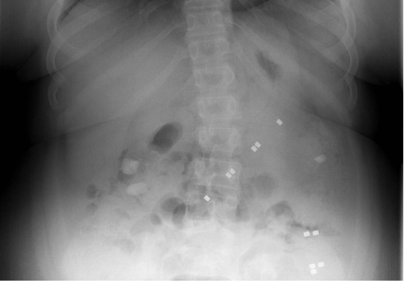

Small, powerful magnets found in certain toys can be particularly hazardous. When swallowed, multiple magnets can attract each other through the intestinal walls, causing severe damage. When discussing toy safety with caregivers, clinicians should advise caution about toys with strong magnets.

This article outlines a clear and concise algorithm on the treatment of magnet ingestion. The most crucial factor in medical decision making is the duration of magnet ingestion. Observation and serial radiographic studies are based on normal small bowel transit time and should not exceed 6 hours.